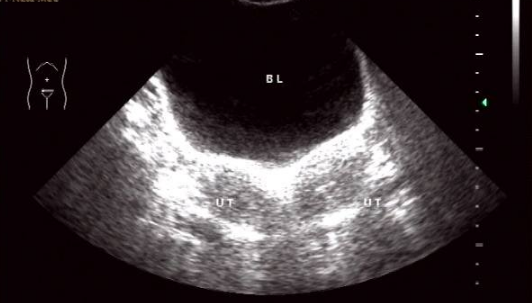

雙角子宮圖片

雙角子宮 (7)